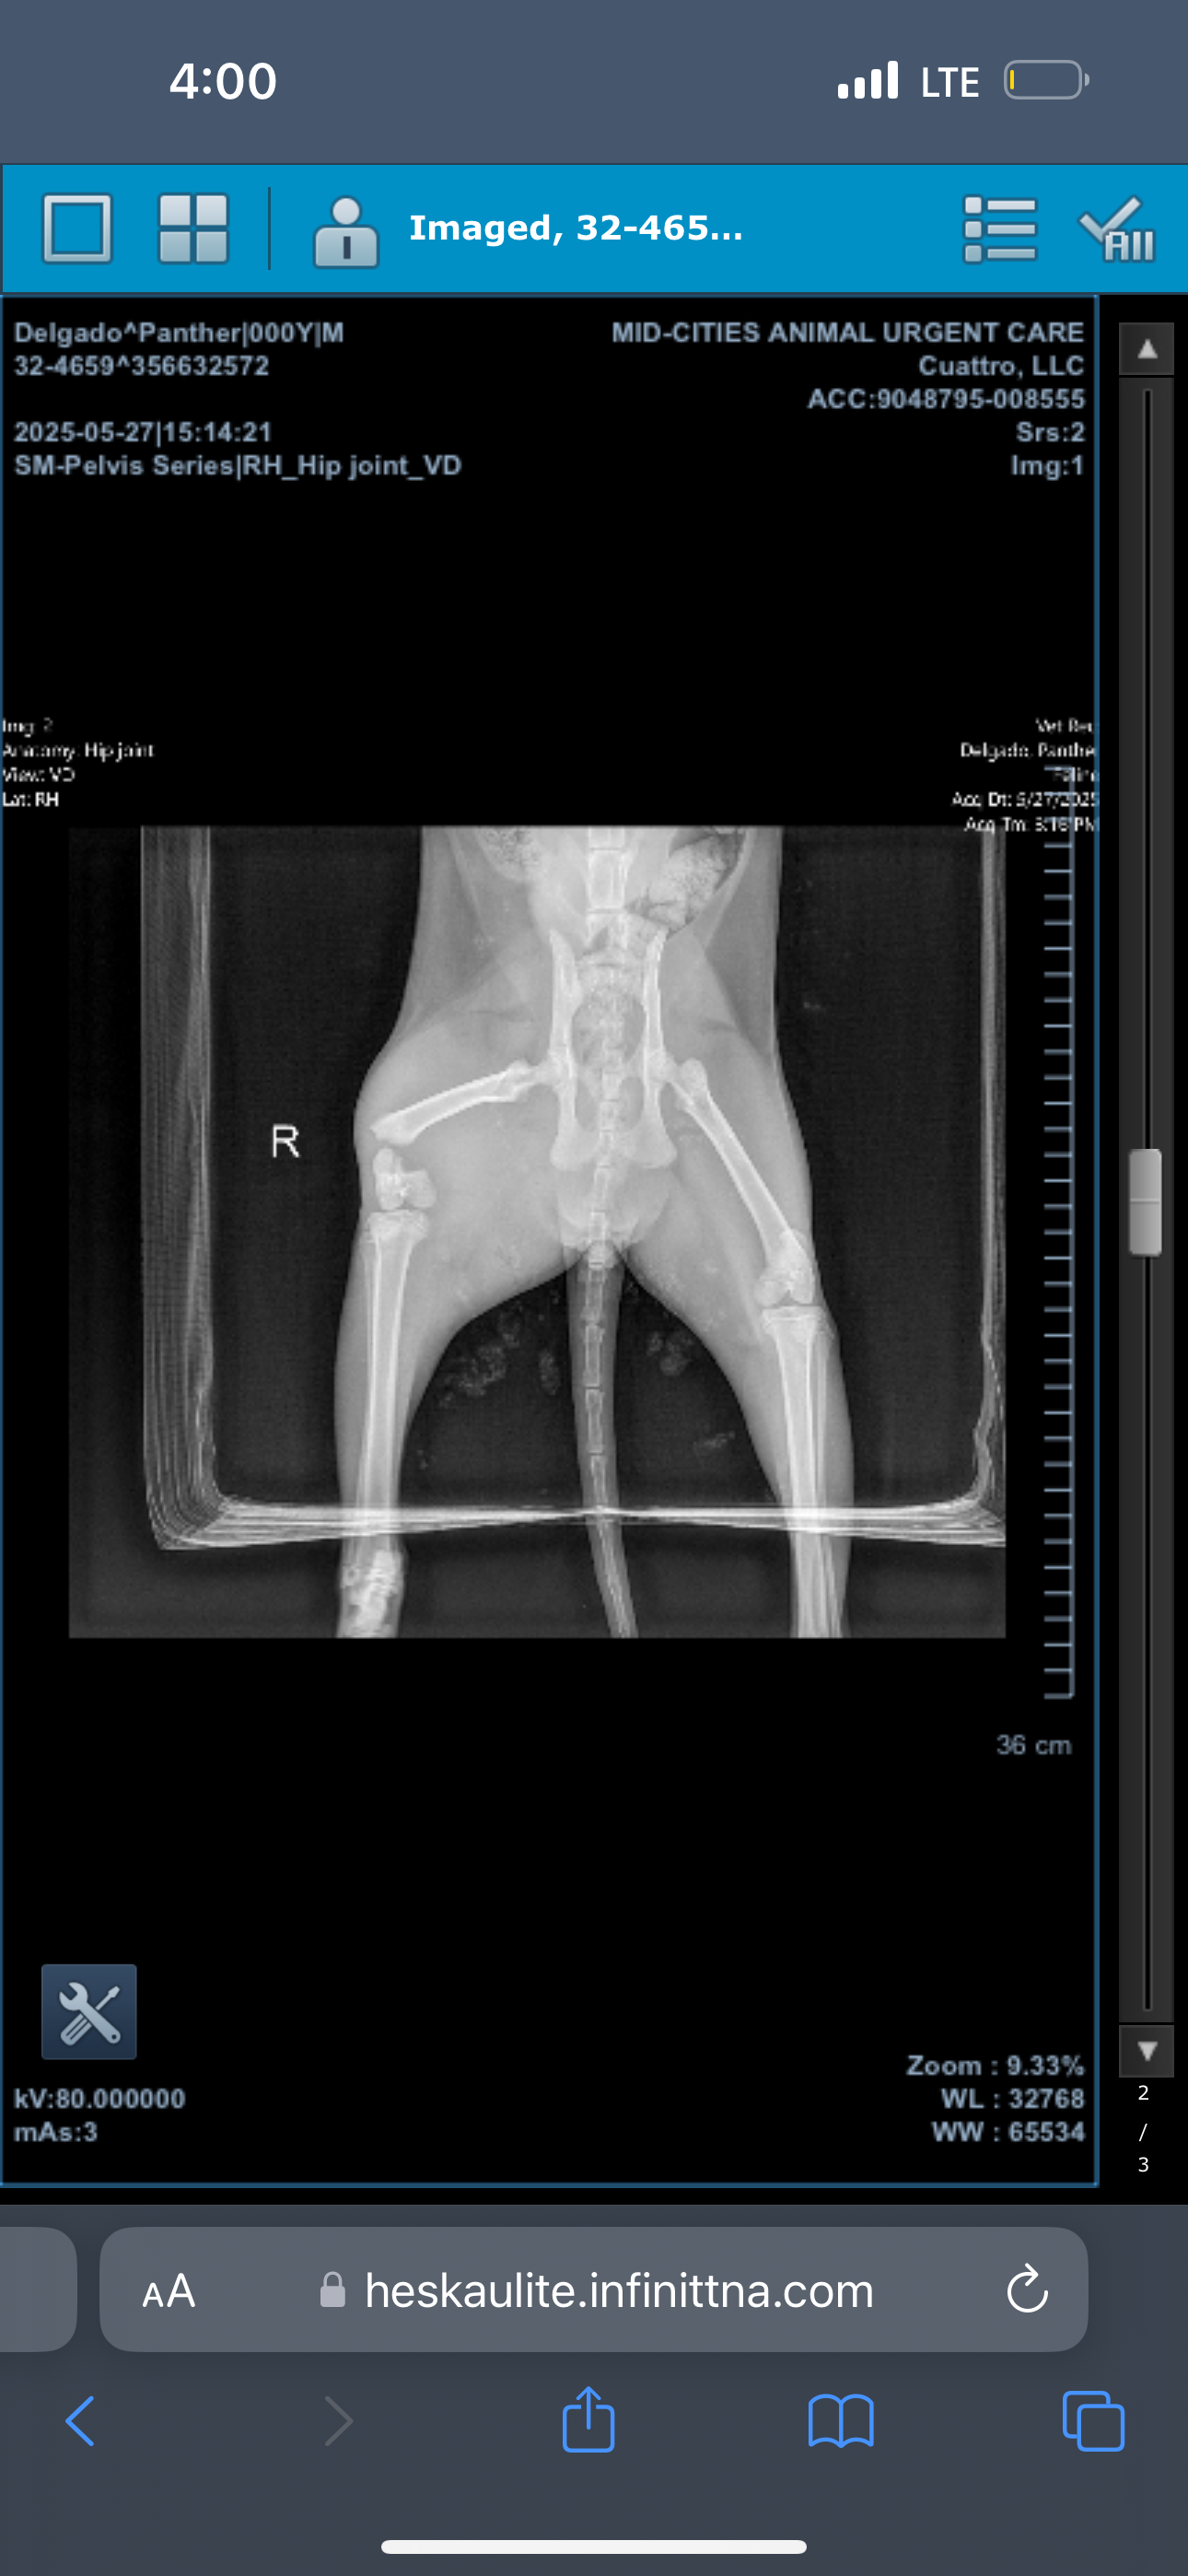

One of my stray babies suffered a car accident a couple of days ago and now has a broken leg that needs medical assistance. I already paid his $300 vet bill, but I had to make a very hard choice of either amputating his leg or putting him to sleep. I do not have the funds to get him a surgery that will only be a possibility of him being able to walk again, so I have chosen to lead with the amputation so his family won’t be separated from him.